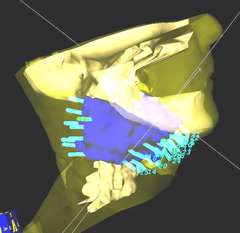

3-D image of an interstitial implant for base of tongue cancer and right neck lymph node. The treatment catheters are aqua and the 100% radiation dose "cloud" is blue. The rapid dose reduction outside the implant, plus HDR’s ability to shape the radiation dose ensures that the doses to normal tissues such as the spinal cord and salivary glands are kept to a minimum.